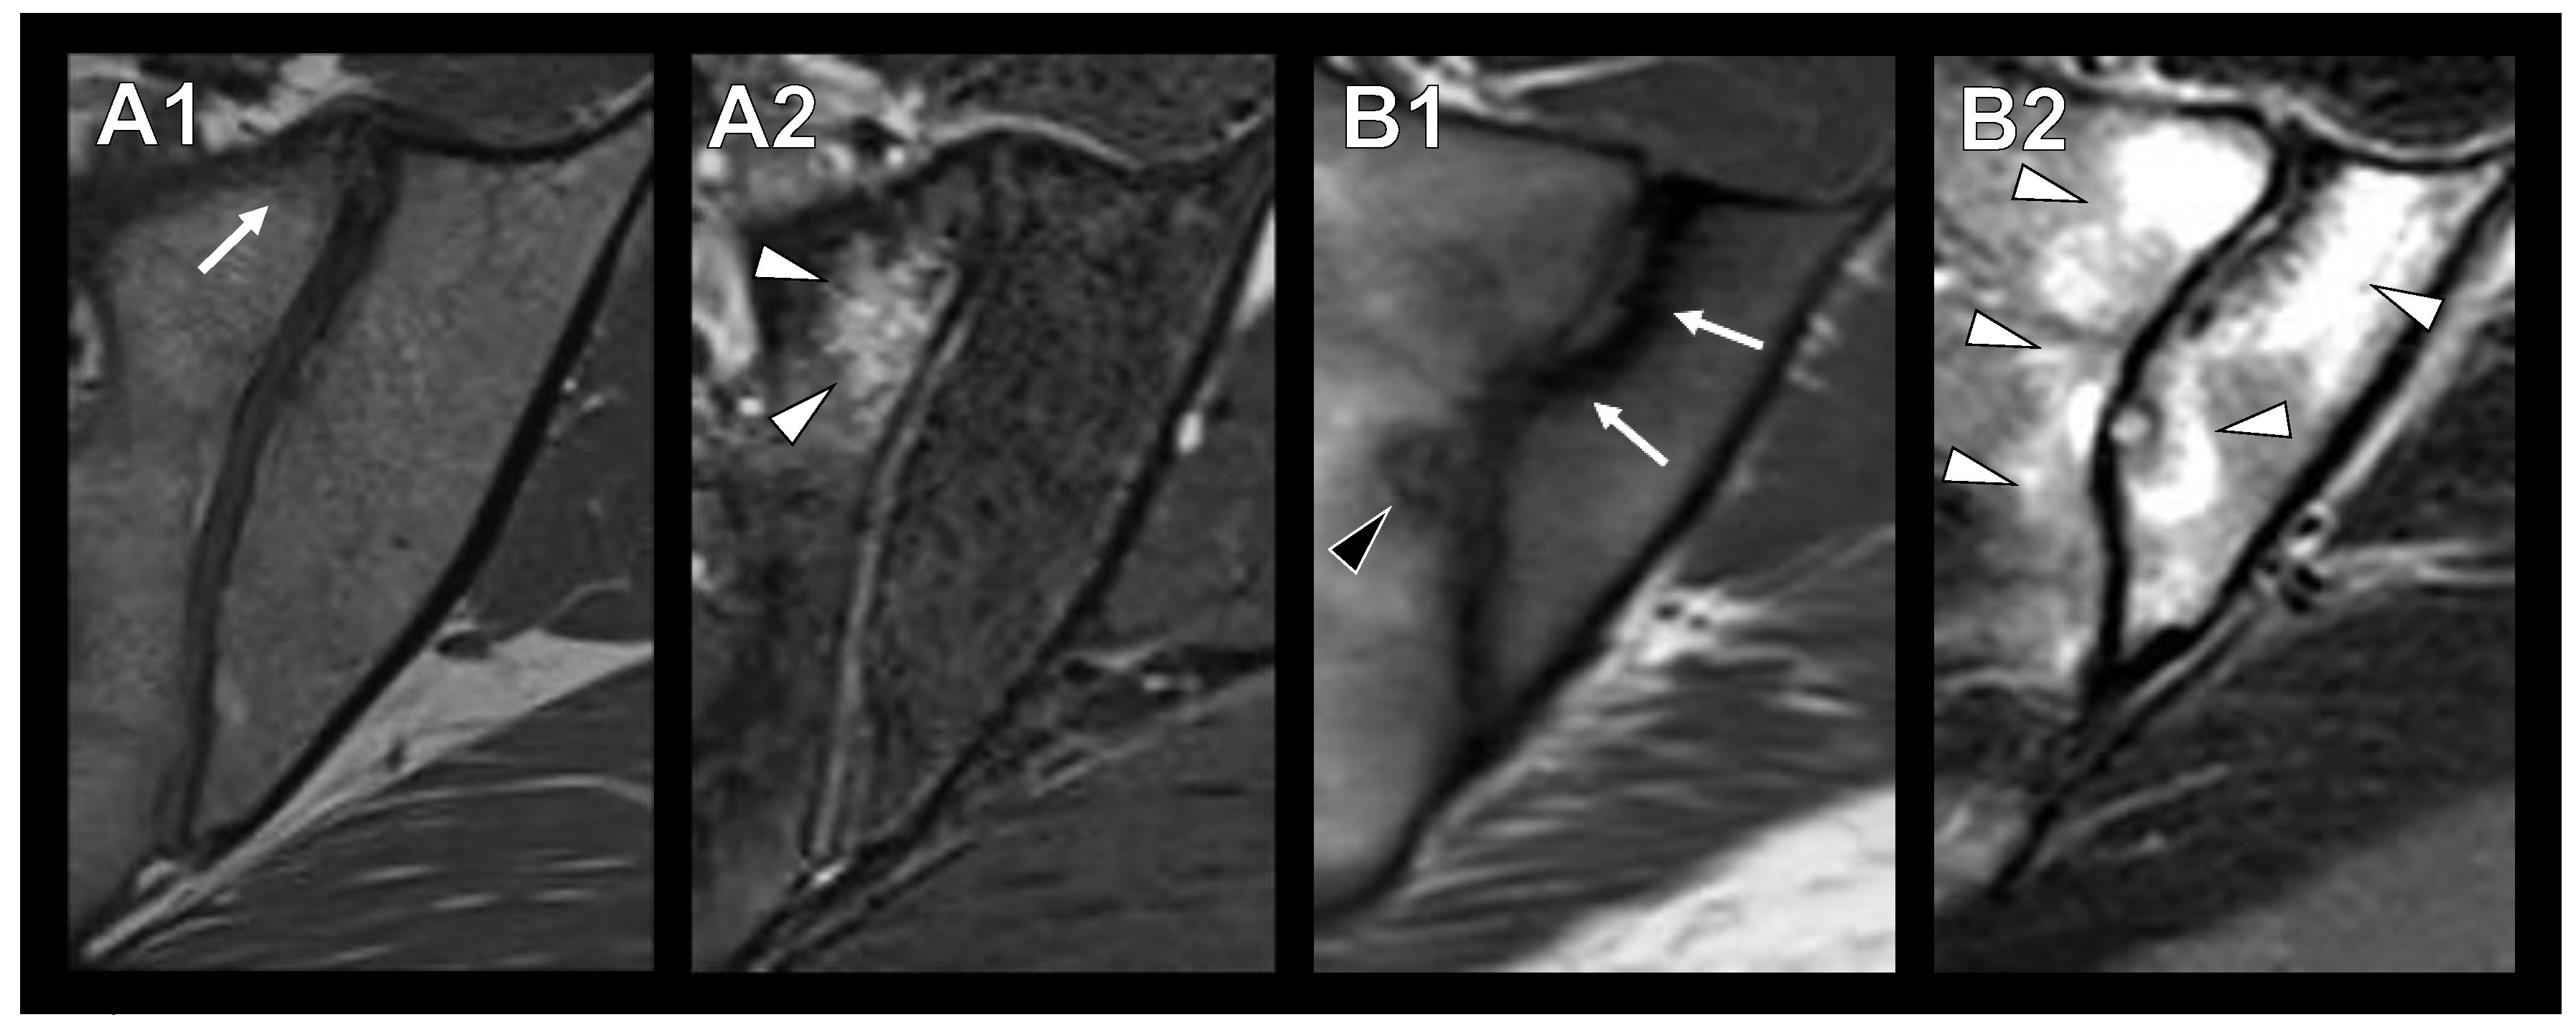

3.2. Sclerotic Lesions in Typical Location of Osteitis Condensans Ilii

3.3. Imaging Modality and Inter-Rater Reliability